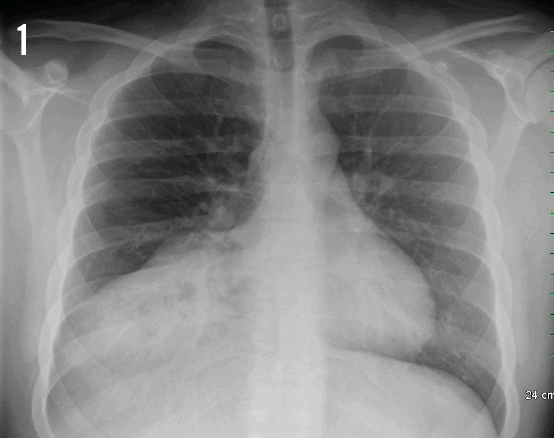

Eric Bugaieski, MD; Shoba Theivanayagam, MD; Venkedesh Raju, MD

A 17-year-old adolescent presented with intermittent hematochezia and right-sided chest pain for one day.